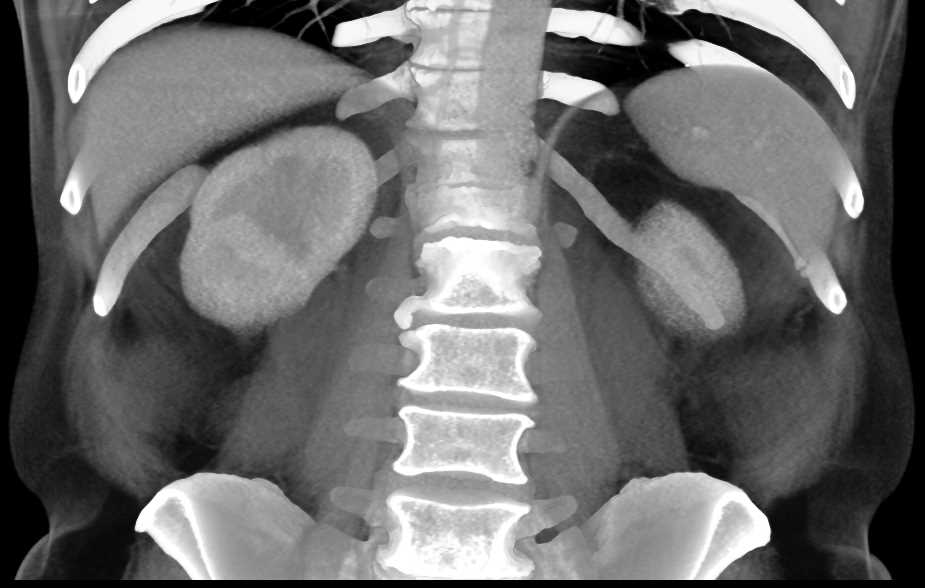

Acute Pyelonephritis Right Kidney